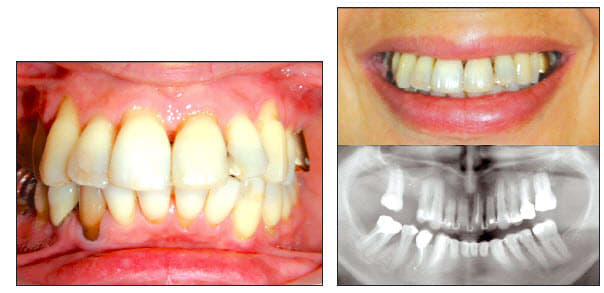

Un mouvement de version coronovestibulaire, avec la couronne qui monte, doit s'accompagner par un mouvement de racine qui part en arriere et vers le bas. De plus le changement d'axe dentaire doit donner sur le pano un raccourcicement de la dent et un eloignement de l'apex du plancher des fosses nasales. Les radios panoramiques montrent exactement le contraire!! On voit bien que l'image d'apex des incisives et des canines se rapprochent du plancher des fosses nasales malgré le changement d'axe, ce qui prouvent qu'une super ingression s'est produite reelement en plus d'une version corono-vestibulaire.